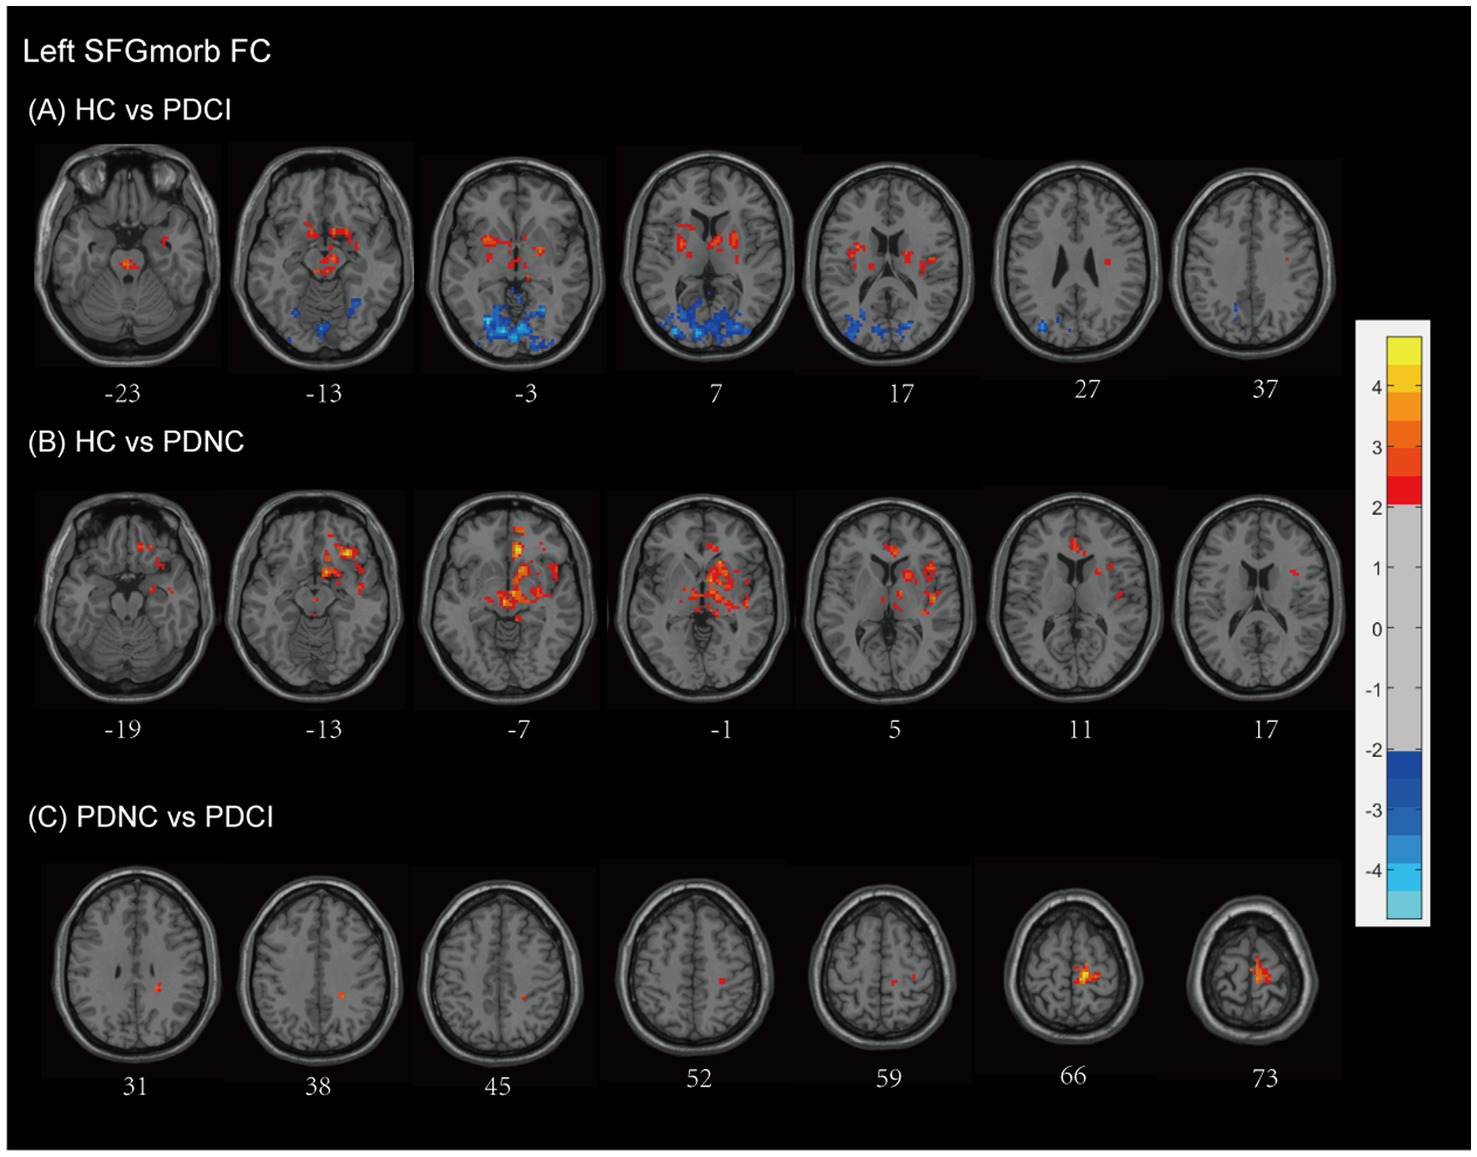

Background &Aims Forecasting specific factors influencing cognitive impairment(CI)in Parkinson's disease(PD)patients can improve clinical outcomes. This study aims to identify brain areas vulnerable to Vitamin D deficiency and assess functional integrity in PD patients with and without CI. Methods Thirty-four PD patients(14 with CI[PD-CI],20 with normal cognition[PD-NC])and 21 healthy controls(HCs) underwent serum vitamin D testing, T1-weighted MRI, and resting-state functional MRI(rs-fMRI). Voxel-based morphometry(VBM)was used to compare gray matter volume(GMV)between PD patients and HCs. Whole-brain multiple regression analyses, adjusted for age and sex, identified GMV regions associated with vitamin D levels. Resting-state functional connectivity(FC)analyses were performed using vitamin D–related regions as seeds. Correlation and multivariate regression analyses, adjusted for Hoehn and Yahr stage and age, assessed relationships among FC, cognitive performance, and vitamin D levels. Results Compared with HCs, PD patients exhibited significant GMV loss, affecting widespread brain regions including the middle frontal gyrus(MFG),superior frontal gyrus(SFG),and hippocampus. Region of interest (ROI)-based analysis revealed that Vitamin D levels were associated with GMV in the bilateral MFG and SFG (r = -0.406, P = 0.021). These findings suggest that the MFG and SFG are vulnerable regions in PD patients linked to Vitamin D levels. To assess the impact of abnormal vitamin D levels on relevant resting-state networks, clusters encompassing the bilateral SFG were used as ROIs. The intrinsic connectivity network of the vulnerable area, using the bilateral SFG as seed regions, revealed abnormal functional connectivity with several brain networks, including the visual network, the default mode network, the executive control network, the sensorimotor network, and the memory network. Abnormal FC values within the SFG functional network were associated with disease severity, cognitive dysfunction, and vitamin D levels (P < 0.05). Multi-model regression analyses revealed that connectivity in the left SFGmed network was negatively associated with CI in PD, with vitamin D levels showing a potential protective effect. Conclusion The SFG is associated with Vitamin D levels in PD patients, and disruptions in its structural and functional connectivity may link to CI. Future longitudinal studies are necessary to confirm these associations and explore the potential impact of vitamin D supplementation on cognitive function in PD.